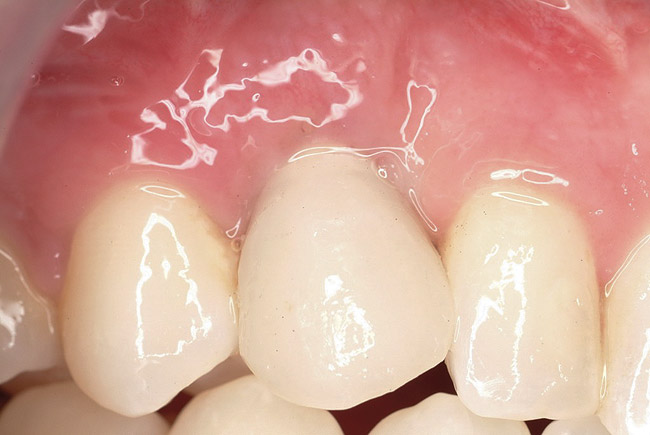

Figure 1  In Case 1, the patient’s edentulous site appeared healthy, with significant keratinized mucosa in the canine position.

Figure 1

A 26-year-old woman presented with a history of trauma combined with an impacted maxillary right canine (No. 6), which was extracted in early childhood. Following two courses of orthodontic therapy—one in her early teens and the second in early adulthood—the area had reportedly been grafted approximately 9 months prior to her initial presentation to the author’s private periodontal practice. Clinically, the edentulous site appeared healthy, with significant keratinized mucosa in the canine position (Figure 1). A cone-beam CT scan revealed severe horizontal bone deficiency in the proposed implant position (Figure 2). Adequate bone height for implant placement was evident; however, the thinnest portion of the ridge measured approximately 0.45 mm in width. It was proposed that an augmentation be performed to facilitate implant placement, which the patient accepted.

Ten weeks after implant insertion, the patient presented to begin soft-tissue contouring via a fixed, provisional crown (Figure 10). Deliberate under-contouring of the cervical portion of the temporary restoration was performed to avoid unwanted mucosal recession and possible esthetic complications (Figure 11 and Figure 12).